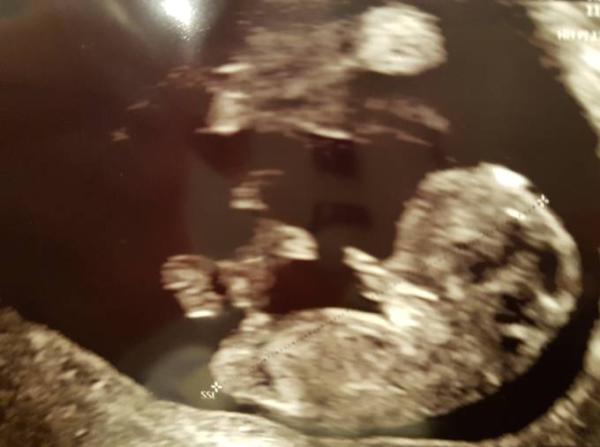

Knappe 3cm kleinstes Wesen mit kräftigem Herzchen

Und die kleinen Fingerchen

die hat man so super gesehen... ich bin gerade schwerst verliebt!!! Jetzt können wir es Weihnachten guten Gewissens allen erzählen.

Beim letzten mal sagte der Arzt es ist 6+2/3 statt 6+6 und diesmal 9+4/5 statt 10+0. Da aber wohl die paar Tage nicht viel ausmachen und sich das kleine super weiterentwickelt hat lässt er einfach den 17.7.18 als ET stehen und ich bin damit spontan in die 11. Woche gerutscht, da ich mich schon mit der korrigierten Version angefreundet hatte